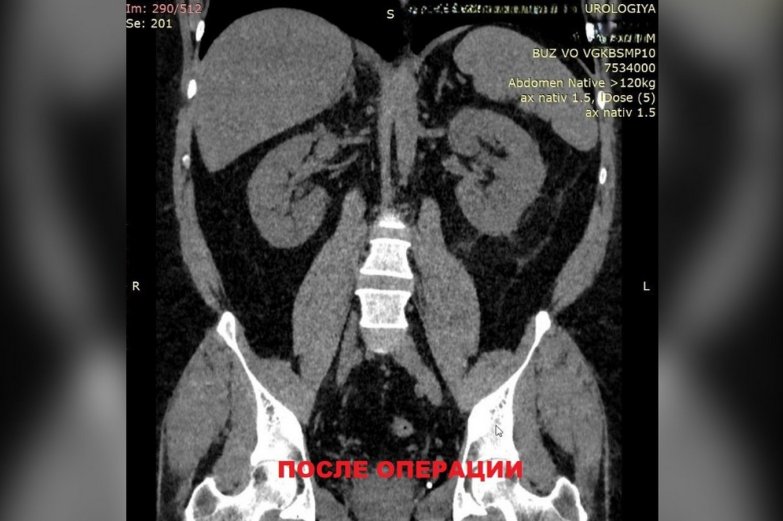

Врачи Воронежской городской клинической больницы скорой медицинской помощи №10 (БСПМ №10) выполнили сложную операцию по удалению камня в почках. В больницу обратился 38-летний воронежец с жалобами на боль в левой части поясницы. Специалисты выяснили, что у мужчины большую часть чашечно-лоханочной системы левой почки занимает камень размером 27 на 39 мм. Отягощающим фактором была избыточная масса тела пациента – он весил 142 кг. Врачи выполнили тяжелую операцию без открытого разреза. Через пять дней пациента выписали домой. Об этом сообщили в пресс-службе регионального министерства здравоохранения в четверг, 4 сентября.

Под контролем УЗИ и рентгена с помощью лазерного излучения камень раздробили на мелкие фрагменты и извлекли их через прокол в поясничной области.